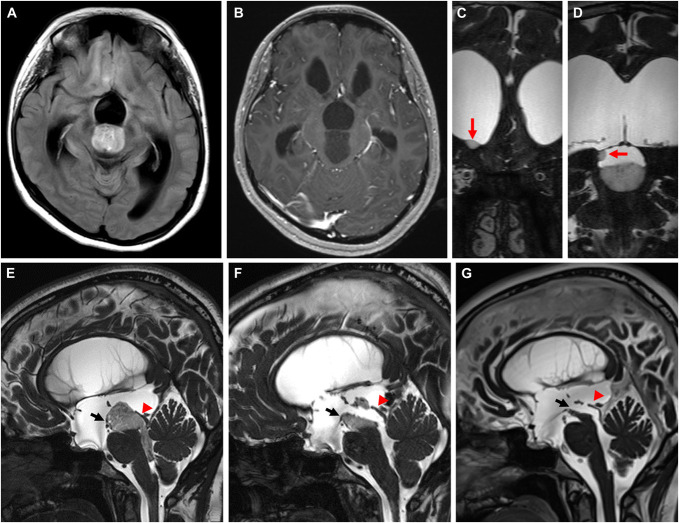

Clinical presentation: A 20-year-old woman presented with mild cognitive dysfunction and marked ventricular dilatation. She had no preoperative symptoms of intracranial hypertension, and her head circumference was more than 2 SDs above the 98th percentile. The aqueduct of Sylvius was entirely occupied by a neoplastic lesion with 2 periventricular nodules at the wall of the third ventricle and anterior horn of the right lateral ventricle. She was treated successfully with endoscopic tumor resection followed by chemotherapy, and the patency of the aqueduct of Sylvius was secured throughout the duration of treatment.